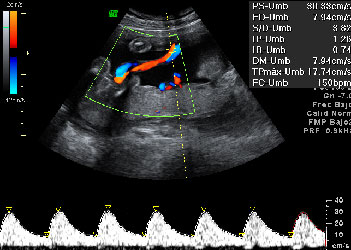

Ecografía: Doppler pulsado del cordón umbilical

La ecografía Doppler estudia el flujo sanguíneo dentro de los vasos. En este caso, se analiza la circulación sanguínea en el cordón umbilical, es decir, como llega la sangre oxigenada de la placenta al feto y el camino contrario, la sangre poco oxigenada del feto a la placenta.

Doppler pulsado del cordón umbilical

En la parte inferior de la imagen se observa un trazado normal del flujo sanguíneo a través de la arteria umbilical (arriba).